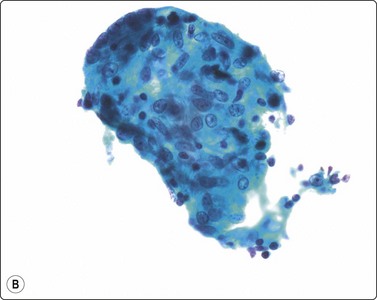

Fungal infections can be associated with granulomas and the yeasts and hyphae may be seen as negative images or variably stained in the Giemsa and Papstain depending on the specific fungus and the degree of degeneration of the hyphae. Cryptococcus may have no granulomas, especially in IC patients, and the 5–15-micron round yeasts may be seen within the cytoplasm of macrophages and MNGC or in the background with narrow-necked budding, a mucicarmine-positive and Giemsa-negative ‘halo-like’ capsule, and variably stained body (Fig. 18.8).43-45 In profoundly IC AIDS patients, there may be no capsule and the distinction from Histoplasma capsulatum relies on culture, as both stain with Giemsa. Histoplasmosis has largely intracellular smaller 2– 5-micron round yeasts showing variable budding in the GMS, and in Papstains appear as ‘holes’ in macrophage cytoplasm (Fig. 18.9).46-48

image image

Fig. 18.8 (A) Cryptococcus yeasts with occasional narrow-necked budding and negative-staining capsule delineated by round body and surrounding serum (Giemsa, ×600); (B) Cryptococcus in mucicarmine stain with positive capsule and occasional narrow- necked budding (Muc, ×600).